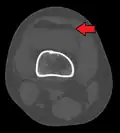

3D reconstruction of a CT image of a tibial plateau fracture -